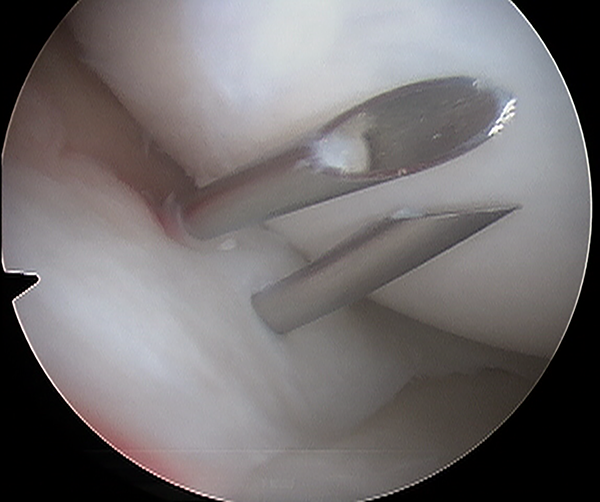

Figura 2:

Por transiluminación se puede facilitar ubicación de la interlinea articular y del punto de acceso a nivel de la ruptura meniscal.

Figura 3:

Vision artroscopica del menisco interno en una rodilla izquierda, se observa el pasaje de dos agujas de sutura meniscal con orientacion vertical.